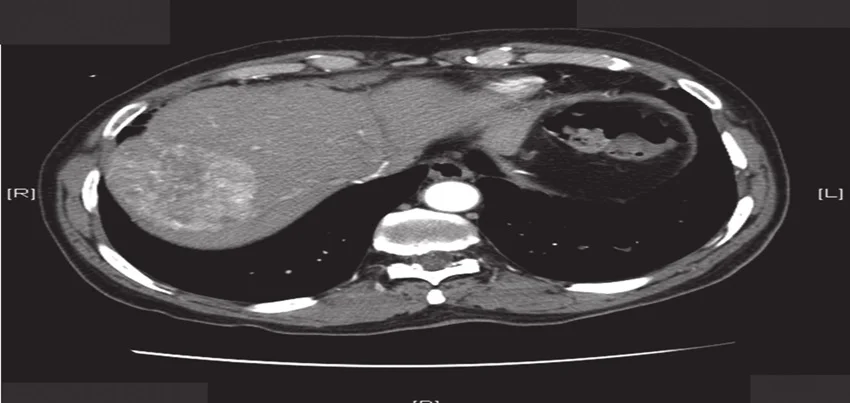

CT Scan of the Abdomen Triphasic Liver

A CT scan of the abdomen triphasic liver is a specialized medical imaging test that allows doctors to evaluate the liver and surrounding organs in great detail. This test combines X-ray technology with computer processing to create highly-detailed images of the liver, which can be used to diagnose and monitor a variety of liver diseases, including cancer, cirrhosis, and hepatitis. In this blog post, we will discuss how this test is conducted, what are the common symptoms for ordering the test, how to prepare for the test, how long does it take, and how the results are interpreted.

A triphasic liver CT scan involves three distinct phases: arterial, portal venous, and delayed phases. During the procedure, contrast material is injected intravenously, followed by sequential imaging at specific time intervals to capture the dynamic enhancement patterns of liver tissues and blood vessels. Radiologists carefully analyze the images obtained in each phase to assess liver morphology, detect abnormalities, and evaluate blood flow dynamics.

High Sensitivity for Tumor Detection: By capturing multiple phases of contrast enhancement, triphasic CT scans provide superior sensitivity for detecting liver tumors, including hepatocellular carcinoma (HCC), liver metastases, and other focal lesions.

Accurate Staging and Characterization of Liver Lesions: Triphasic CT scans facilitate accurate staging and characterization of liver lesions, helping clinicians differentiate between benign and malignant tumors, assess tumor vascularity, and plan appropriate treatment strategies.

Evaluation of Liver Function and Parenchymal Abnormalities: By visualizing liver enhancement patterns and parenchymal abnormalities in different phases, triphasic CT scans provide valuable insights into liver function, perfusion, and tissue composition.